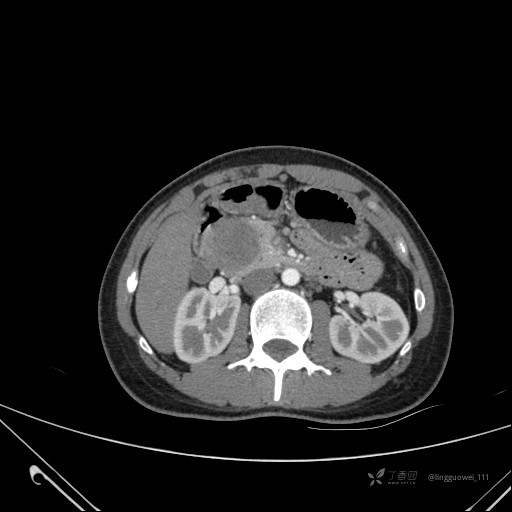

患者性别:女

患者年龄:28岁

主诉:体检发现胰腺病变,行 CT检查。

动脉期: